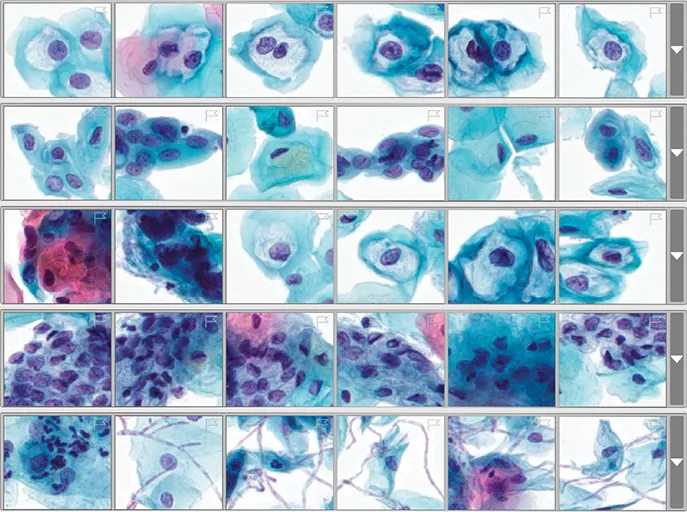

Genius Cervical AI narrows your screening from tens of thousands of objects down to a curated gallery of images for targeted and efficient review.

Genius Cervical AI objectively analyzes every cell on a digital image and intelligently identifies those clinically relevant.

A single gallery representing the entire case is organized and presented, enabling reviewers to make an interpretation using only the AI-generated gallery of images.

The system can rapidly analyze all cells on a ThinPrep® Pap test digital image, narrowing tens of thousands of cells down to an AI-generated gallery of the most diagnostically relevant images. This will help provide healthcare providers with the critical information they need to guide earlier detection and better treatment decisions for the patients they serve.

A new, deep learning-based artificial intelligence algorithm that is designed to detect pre-cancerous lesions and cervical cancer cells.